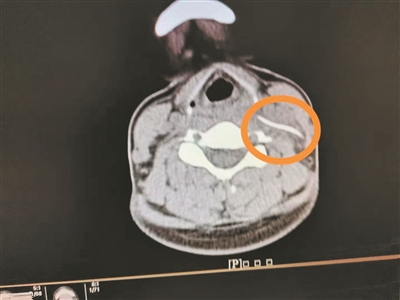

影像检查显示颈部异物。

4月1日,陈女士带女儿到南方医科大学第三附属医院就诊,想起自己颈部不舒服,就顺便到耳鼻咽喉科就诊,副主任医师曹庆硕接诊后,请患者平躺检查,此时陈女士感觉颈部更痛了,医生怀疑颈部有异物,于是进行了颈部CT平扫,果然发现左侧颈动脉鞘区有异物。